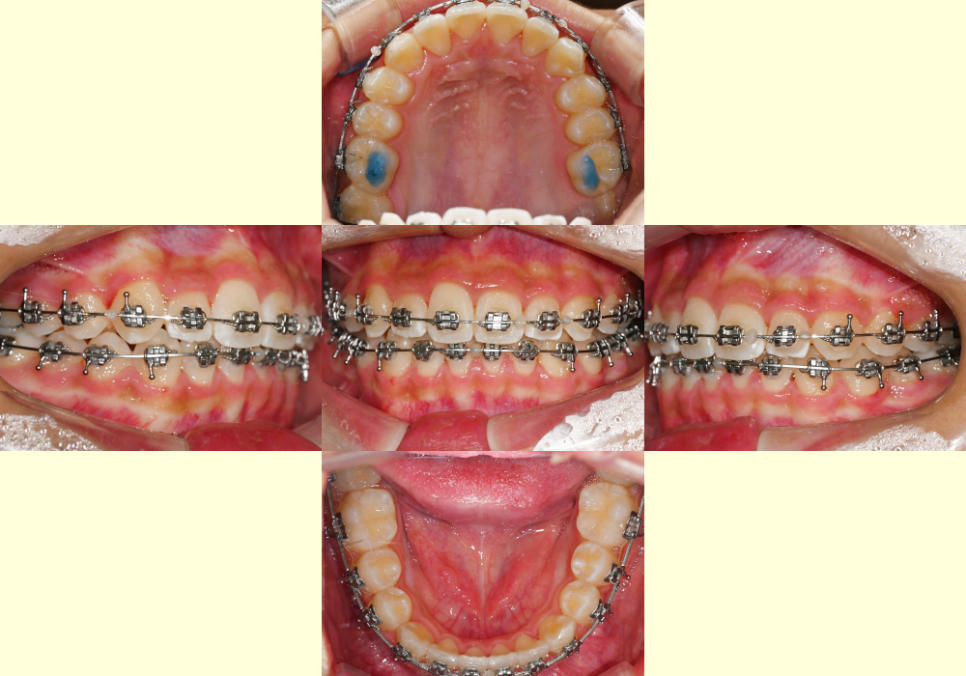

24.05.17

이후 아랫니에도 브라켓을 부착하여

이를 이동하여 치열 개선합니다.